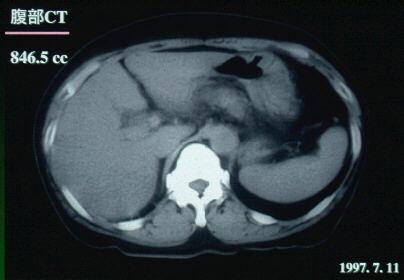

1997.7.11(入院時):腹部CTスキャン

肝容量846.5ccと減少。